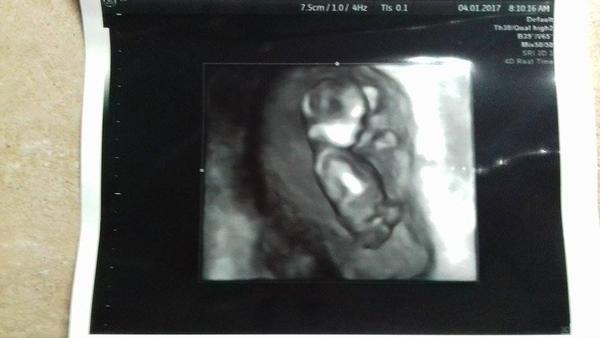

tak ako som slubila pridavam fotku mojho drobceka 🙂